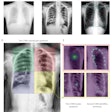

Occlusion maps identifying key features in representative chest x-rays with high and low diagnostic scores. Dark green pixels highlight significant features for model prediction, primarily associated with cardiomediastinal, upper abdominal, lower neck, and supraclavicular regions. Examples of CXRs with high and low diagnostic scores are presented. Image and caption courtesy of Nature Communications through CC BY 4.0.

Occlusion maps identifying key features in representative chest x-rays with high and low diagnostic scores. Dark green pixels highlight significant features for model prediction, primarily associated with cardiomediastinal, upper abdominal, lower neck, and supraclavicular regions. Examples of CXRs with high and low diagnostic scores are presented. Image and caption courtesy of Nature Communications through CC BY 4.0.The prospective test dataset of 9,943 images included 8,382 (84.3%) patients with no type II diabetes, 1,119 (11.3%) who had controlled disease, and 442 (4.4%) with poorly controlled disease. According to the findings, the model effectively detected type II diabetes with an area under the receiver operating curve (AUC) of 0.84 and a 16% prevalence. The model flagged 1,381 cases (14%) as suspicious for type II diabetes.

Finally, the authors noted that the occlusion maps generated to display the basis for the DL model's decisions corresponded significantly to known fat distribution features for the disease in the central chest, lower neck, upper abdomen, and axillary regions.